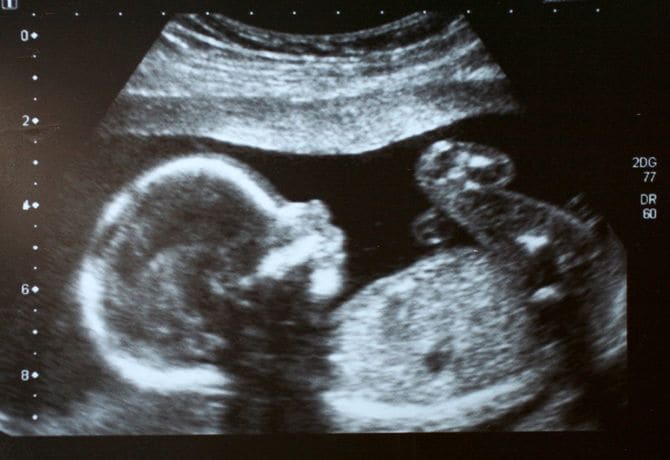

そんな慌ただしい日々の2021年3月。近藤さんが2人目の妊娠をしたことがわかる。

義母の認知症が発覚したとき、近藤さん夫婦は2人目を計画していた。待ったなしの義母の介護がばたばたと始まり、近藤さんは2人目をどうするか悩んだ。最終的な結論は、「介護で2人目を諦めたくない」。妊活を継続したのだった。